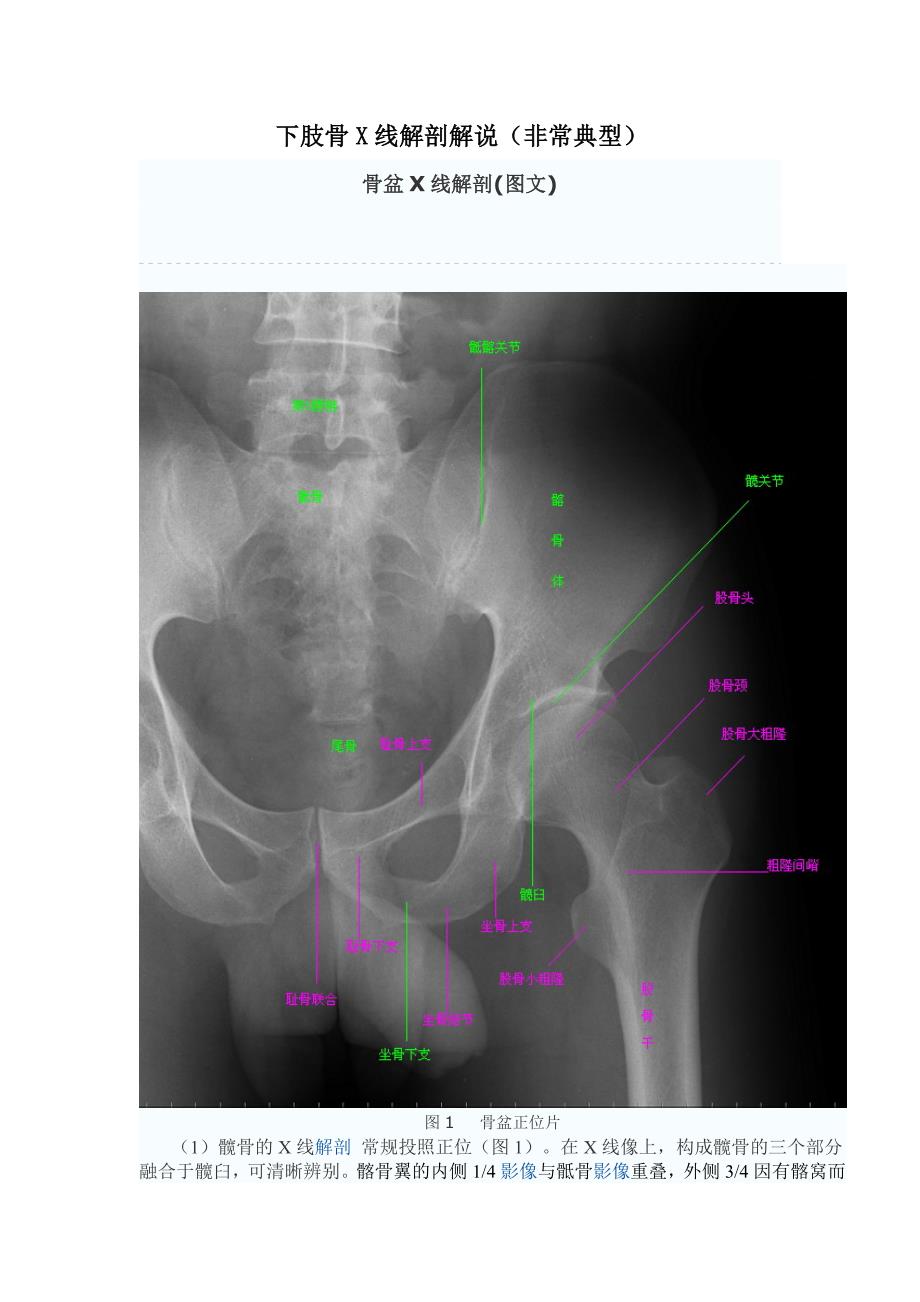

下肢骨X线解剖解说(非常典型)骨盆X线解剖(图文)图1    骨盆正位片(1)髋骨的X线解剖  常规投照正位(图1)在X线像上,构成髋骨的三个部分融合于髋臼,可清晰辨别髂骨翼的内侧1/4影像与骶骨影像重叠,外侧3/4因有髂窝而较透亮髂嵴阴影较致密,边沿不光滑,外侧可见髂前上棘影,髂后上棘则重叠于骶骨影内弓状线及骨盆腔内侧壁形成复合影像,外侧可见弧形的髋臼阴影髋臼阴影的上段粗而致密,中段较细,它向下绕过髋臼切迹前部的下缘,与耻骨体的内面形成一条“U”形的致密线,称为泪滴线(Koekler泪滴),泪滴线二脚之间的距离,即髋臼窝的厚度髋臼内下方的透亮影为闭孔闭孔影的上界是耻骨上支、外侧界是坐骨体的下份,坐骨结节阴影与其重叠坐骨棘的阴影呈三角形突向盆腔 (2)骨盆的X线解剖  骨盆一般投照前后位,检查骶、尾骨时可加照侧位,检查骶髂关节时应加照45°斜位,产科骨盆测量另有其特殊投照措施骨盆前后位片上,骶骨中线应通过耻骨联合骶髂关节左右对称,关节间隙下半部分可以显示,上半部常投影出模糊双线影界线的影像在女性呈卵圆形,在男性略呈鸡心形髂嵴连线影正好通过第4、5腰椎间隙由髂嵴影向外可追踪到骼前上、下棘,由髂前下棘到股骨颈外上缘的连线称髂颈线,用以鉴定髋关节与否正常。

正位片上,可以测量耻骨下角,男性为锐角,女性为钝角女性骨盆径线的测量,可以采用正位(见图1)和侧位正位片上,界线影像最远点连线为入口横径,正常为12.3cm;两侧坐骨棘连线为中骨盆横径,正常为10.5cm;两侧坐骨结节间距为小骨盆出口横径,正常为11.8cm侧位片上,耻骨联合后缘上端到骶骨岬连线为小骨盆入口前后径,正常为11.6cm;耻骨联合后缘下端和坐骨棘中点的连线延长到骶骨的前缘,为中骨盆前后径,正常12.2cm;耻骨联合后下缘到骶尾关节的连线,为小骨盆出口前后径,正常11.8cm3)髋关节的X线解剖  常规拍摄正位(见图1)和侧位X线片正位线片上,因髋臼三骨之间以“Y”形软骨相连,融合之前,体现为横行带状透亮影,其宽窄随着年龄变化而变化年龄越小此透亮带越宽;年龄越大,透亮带变窄,15~17岁左右消失股骨头大部套在髋臼内,表面光滑,为致密的细弧线头的中心偏后下部有一小凹陷,是股骨头凹,有时可投影到股骨头弧线内侧,显示为小环形透亮圈侧位片上,中央的凹窝是髋臼,呈半圆形的致密线.腕关节及手X线解剖(图文)  来源:影像园  作者:admin 【复制分享】【讨论-纠错】【举报】图1  手骨及腕关节X线像    腕骨的X线解剖  常规X线片涉及腕部后前位及侧位片。